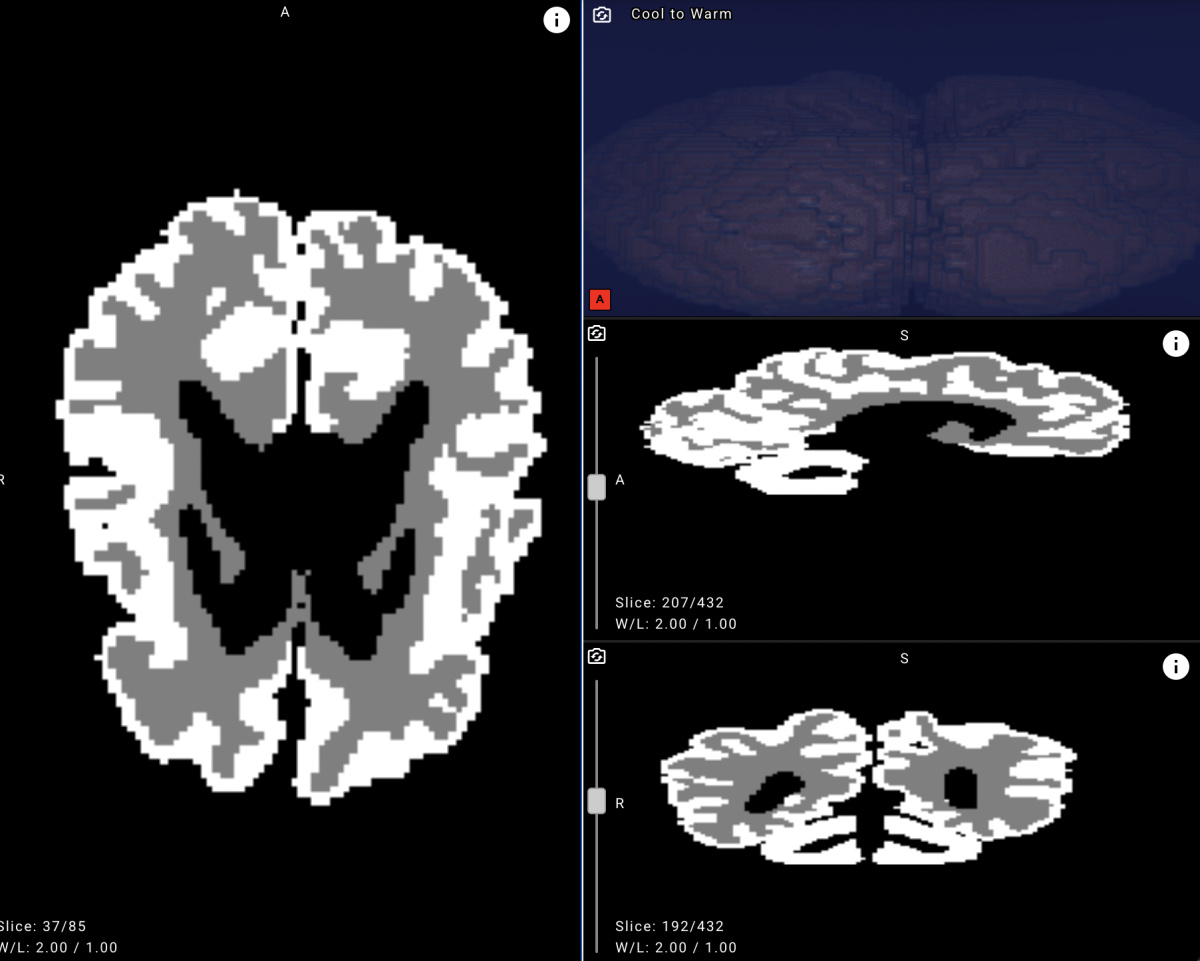

Новую систему разработали специалисты Центра технологий для общества Yandex Cloud и студенты ШАДа, совместно с Санкт-Петербургским педиатрическим медицинским университетом. Эксперты обучили нейросеть на 1500 обезличенных МРТ-снимков пациентов университета и на открытом наборе данных, предоставленном в рамках международного конкурса по сегментации МРТ-изображений головного мозга младенцев MICCAI Grand Challenge. Для автоматической разметки применялась модель BIBSNet (Baby Intensity-Based Segmentation Network). Для сегментации изображений применили две нейросети: ResNet и U-Net. Специалисты Yandex Cloud предложили архитектуру решения, протестировали и настроили веб-сервис. Позднее разработку планируют выложить в открытый доступ, чтобы её могли использовать в медицинских и других проектах по всему миру.